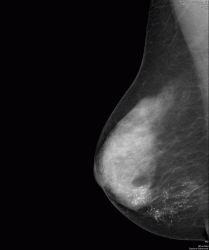

А вот и снимок в прямой проекции

Конечно, на представленнолй маммограмме четко дифференцируется "утолщение контура" (кожи) параареолярной области. А какие еще признаки, которые свидетельствует об "раке Педжета", имеют место быть на представленном изображении?